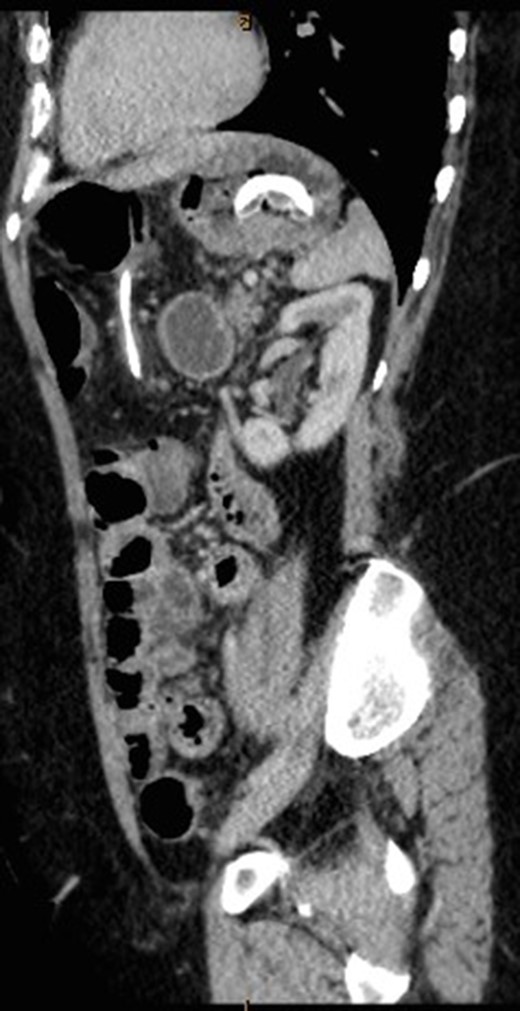

CT abdomen with oral and intravenous contrast was organized to further investigate the tubular foreign body. It revealed concurrent gastric band erosion into gastric lumen and connection tubing eroding into the posterior wall of transverse colon and exiting inferiorly (Figs 2–6). There was no evidence of any oral contrast leak from the stomach.

Sagittal view of CT abdomen showing the gastric band tubing eroding into posterior wall of transverse colon and exiting inferiorly.